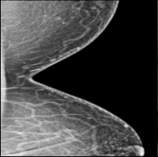

CVAE, as previously observed, performs poorly in detecting outliers with cardiac loop recorder, improper radiography and atypical lesions/calcifications (Figures 3 and S3). The presence of bright regions (unrelated to cancer tissue) is a common feature of these poorly recognized outliers (Figure 1); as a result, it is natural to utilise the presence of such regions as a signal of outliers. The major steps are shown in Figure 4 where an outlier image due to improper radiography (Figure 4A) was first converted to a white-black binary image thresholded by some fixed pixel value (Figure 4B), and then eroded such that only the bright region remains (Figure 4C). The image is more likely to be an outlier if the remaining region is larger. Detailed methodology can be found in Section 2.8.

A

Refer to caption

B

C

D

E

F

Figure 4: Image processing techniques for outlier detection. Panels A, B and C show the image erosion process for outlier detection. A fixed threshold transforms the original outlier in Panel A into the binary image in Panel B. Panel B’ scattered signal gets eroded, as demonstrated in Panel C. Outliers present a large bright region in Panel C. Panel D, E, and F show how to perform pectoral muscle analysis for outlier detection. Panel E removes the pectoral muscle region of the original outlier in Panel D, and Panel F displays the major lines in the pectoral muscle region. A higher number denotes an anomaly.

There is a unique subgroup of improper radiography outliers with very diverse pectoral muscle region. Such an outlier is seen in Figure 4D, and it is found by first cutting the pectoral muscle region out (Figure 4E) and then counting the major line number in the pectoral muscle region (Figure 4F). The greater the number, the greater the likelihood that the image is an outlier. Detailed information can be found in Section 2.8.